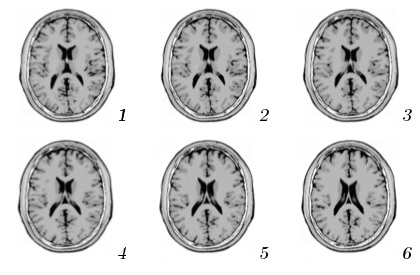

For the brain database, an interesting result is that the distance between brain slices that are physically close is shorter than the distance between slices wide apart in the brain. In other words, if we consider the brain MRI as a volumetric image for which each slice in the database is the result of fixing to some value, then the expectation of the distance between two slices separated along the axis by a distance ,

| (3) |

is an increasing function of for sufficiently close to zero. Fig. 4 shows the evolution of (with two dashed curves providing the 99% confidence interval on estimation) computed over the 100 brain slices rotated and scaled. The expectation of the distance is indeed increasing for . This means that the distance between ISH truly reflects the difference between visual contents. The MRI was indeed taken with a resolution of 1mm for which visual contents of contiguous slices are very close, as depicted in Fig. 4. The false positive pairs of images are therefore more likely to be adjacent slides which are visually close than totally different slides.